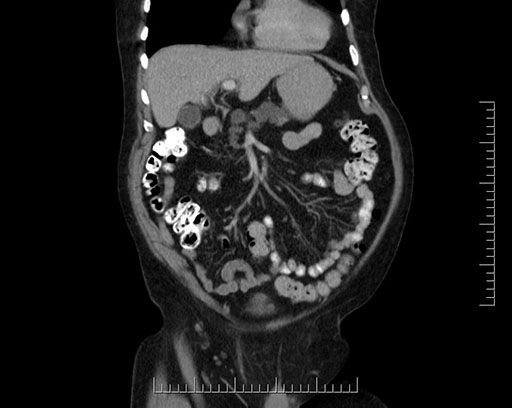

Imaging Analysis

Look through the patient's CT scan to identify any areas of concern for the necessary procedure.

Based on your CT findings, which issue(s) would give reason for "planned slowing down moment(s)" in this case?

Considering a standard Whipple procedure, what step(s) of the operation would you do differently in this case?